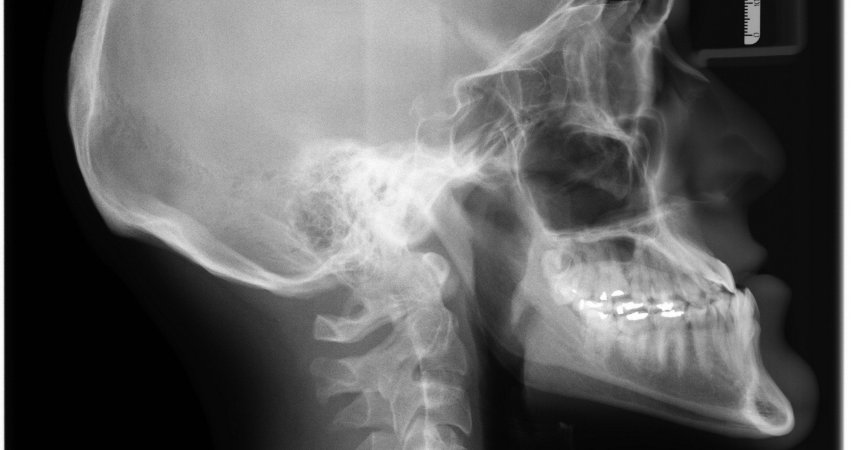

Czytaj WięcejZdjęcia rentgenowskie zębów są ważnym narzędziem stomatologicznym, często używanym do zdiagnozowania problemu, lub po prostu uzyskania obrazu ogólnego stanu zdrowia jamy ustnej. Dlaczego więc zdjęcia rentgenowskie zębów są tak ważne i co one robią? Czego możesz się spodziewać...